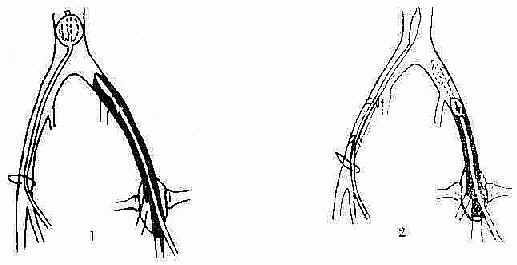

1. 静脉血栓取除术 适用于病期在3日以内的中央型和混合型。可切开静脉壁直接取栓,现多用Fogarty带囊导管取栓,手术简便(图2-121)。

(1)通过右下肢大隐静脉分支,插入第一根Fogarty导管至下腔静脉,鼓张气囊,以防栓塞;从左下肢股静脉切开插入第二根导管达血栓近侧。

(2)鼓张左侧第二根导管的气囊后,连同气囊,缓缓地拉出。萎瘪第一根导管的气囊,恢复血液回流。

图2-121 髂股静脉Fogarty导管取栓术